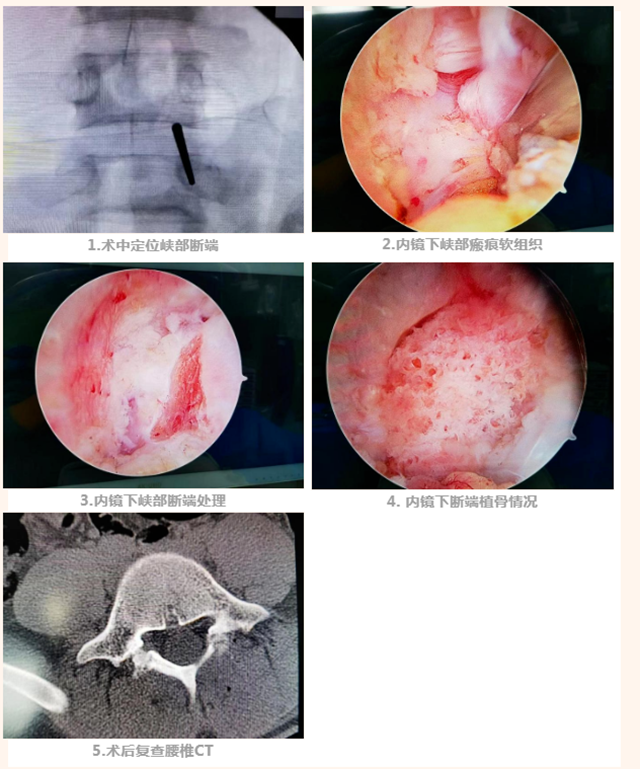

术中及术后如下图:

1.术中定位峡部断端

2.内镜下峡部瘢痕软组织

3.内镜下峡部断端处理

4. 内镜下断端植骨情况

5.术后复查腰椎CT